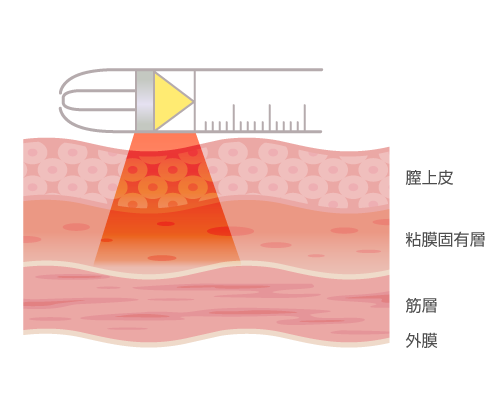

同じインティマレーザーですが「レノバレイズ」と呼ばれる性交痛を改善するモードでの照射が行われます。

膣壁に弾力をつけることで、乾燥しにくい環境を整えていく治療です。

レノバレイズは、膣粘膜の深い層にまでエネルギーが届き、小陰唇や膣の入り口~奥までの広い範囲を施術することが可能です。

また最近では3Dレーザーといってアップグレードバージョンで、複数の波長のレーザーを照射することにより1回での施術による治療効果をレノバレイズよりさらに高めるレーザーも出てきています。